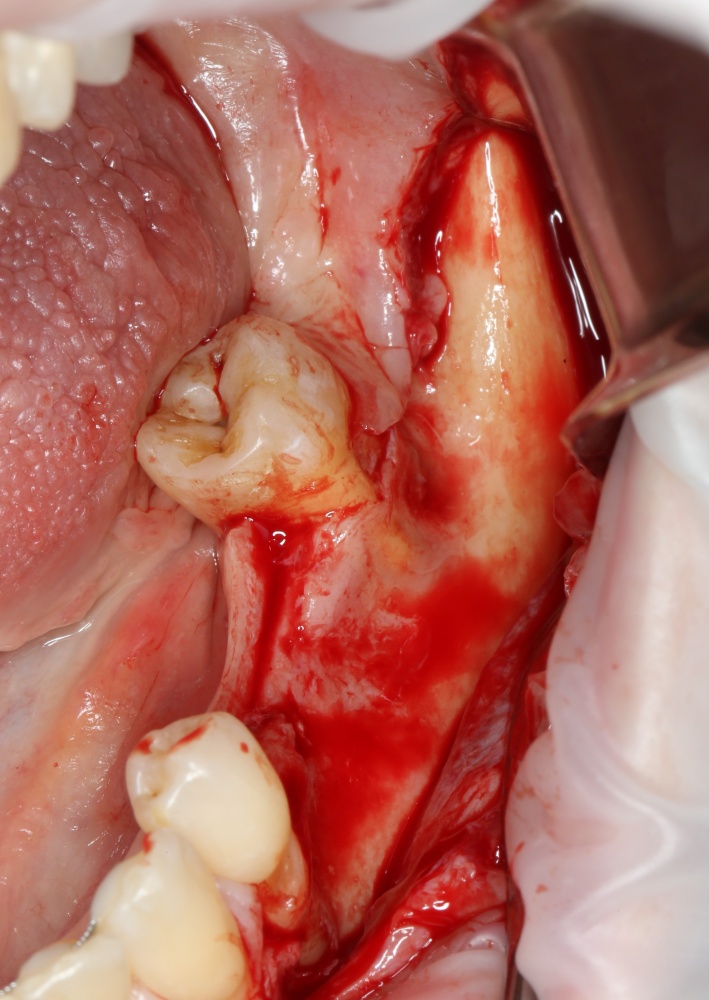

Но вот проблема — при длительном отсутствии зубов, травматичном удалении или из-за воспалительных процессов костная ткань альвеолярного отростка нижней челюсти атрофируется, меняет свою конфигурацию. Иногда довольно значительно:

A09A6305 (2) A09A6306 (2)

Можно ли в таких условиях поставить импланты? Скажу честно, можно. Но эти импланты будут короткими и тонкими, а находиться будут в таких положениях, в которых ортопеду будет очень сложно (иногда даже просто невозможно) их нормально протезировать.